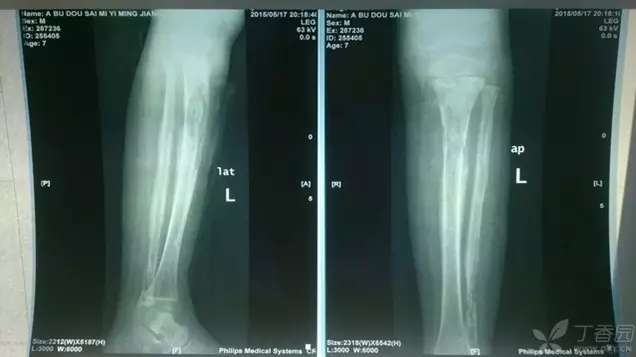

1.2 骨髓炎的溶骨透亮影

患者男,7 岁,于 2015 年 3 月 8 日无明显诱因出现左小腿肿痛,发热。诊断胫腓骨骨髓炎,伴胫骨上段、腓骨下段病理性骨折。